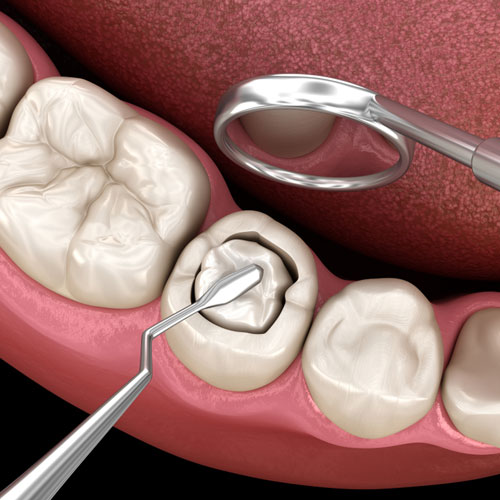

Cleaning & Disinfection

The infected or damaged pulp is carefully removed. The root canals are then cleaned, shaped, and disinfected to eliminate bacteria and prevent further infection.

Filling & Sealing

Once the canals are thoroughly cleaned, they are filled with a biocompatible material to seal them and maintain the tooth’s internal structure.